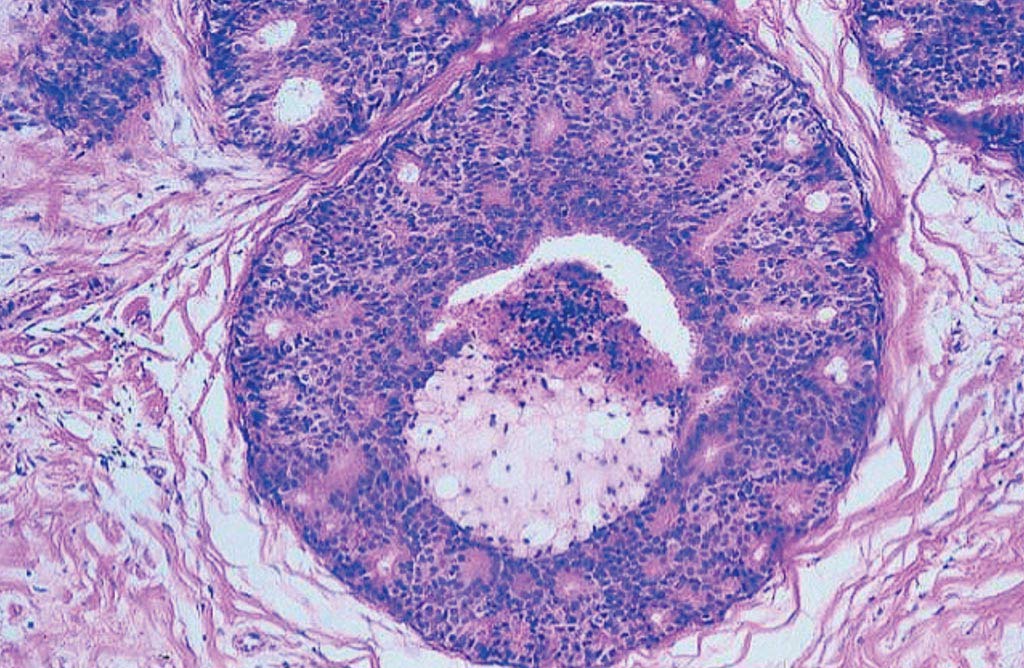

Фотографии опухоли медуллярной аденокарциномы

Раздел: Снимки-откровения